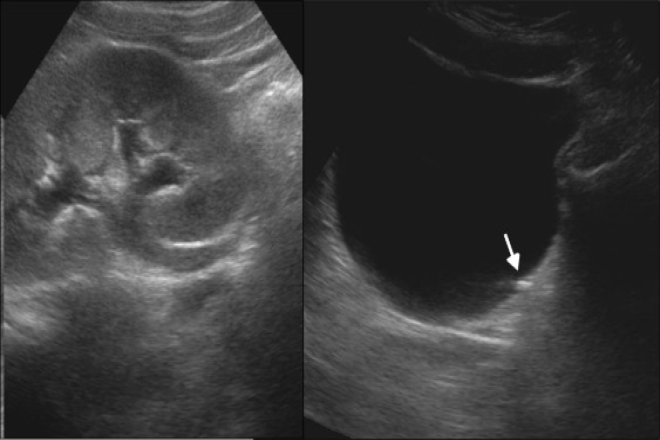

Actualmente, gracias a los avances tecnológicos en ultrasonido, es posible evaluar de manera adecuada las masas renales. Entre los hallazgos más importantes se encuentra una lesión sólida o compleja mayor a 6 cm de diámetro. En cuanto a la ecogenicidad de la lesión, se pueden clasificar en diferentes grados dependiendo de su relación con el parénquima renal. Las calcificaciones, presentes en un 8 a 18% de los casos, pueden ser indicativas de tumores malignos.

El diagnóstico diferencial por ultrasonido incluye distintas patologías como lesiones quísticas, adenomas, infartos renales, entre otros.